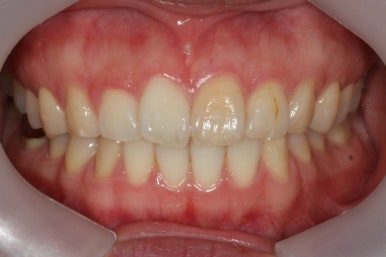

부산앞니교정 키다리아저씨치과에서 시행한 이번 MTA 부분교정의 전후 비교입니다.

위아래 앞니가 가지런해졌고, 작은 앞니의 얼룩무늬도 없어졌네요.